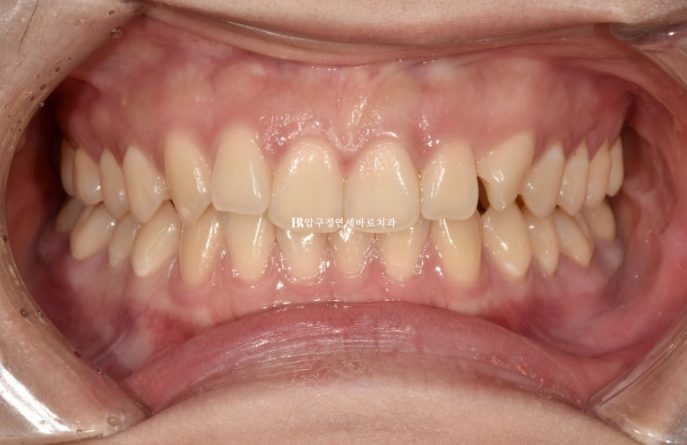

24.11

물샐틈 없는 교합이 보입니다.

마지막 1-2주는 장치를 앞니쪽만 남기고 어금니쪽을 잘라내어 자연스러운 교합안정화를 도모했습니다.

인비절라인은 교합이 안 좋게 끝난다는 편견을 깨기 위해 이렇게 포스팅을 작성합니다.